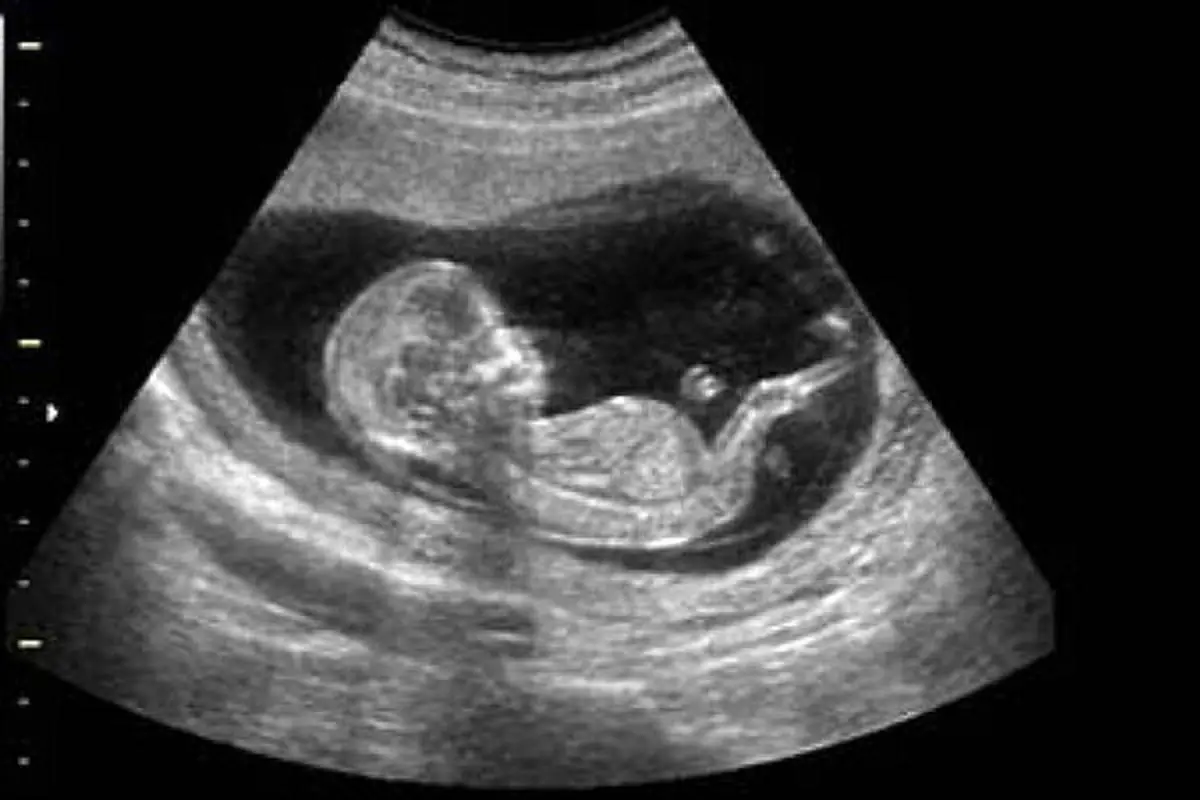

کارگردان «جاده‌های برقی» در توضیح این مساله که چرا سونوگرافی باعث افزایش تعداد نوزادان پسر شده است، بیان کرد: خانواده‌هایی که به دنیا آمدن فرزند پسر برای‌شان بسیار مهم است، وقتی در سه ماهگی یا ۲ ماهگی متوجه جنسیت جنین دختر خود می‌شوند، به راحتی به سمت سقط می‌روند یا از طریق رژیم غذایی، تزریق آمپول یا کاشت تخمک به پسر شدن فرزندشان کمک می‌کنند. این مستند موضوع‌محور به تعیین جنسیتی اشاره می‌کند که به دست بشر افتاده و عامل نابود شدن موازنه جنس جنین در جهان است.